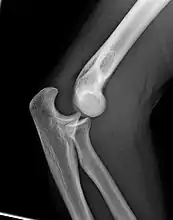

Normal radiograph; right picture of the straightened arm shows the carrying angle of the elbow

When the arm is extended, with the palm facing forward or up, the bones of the upper arm (humerus) and forearm (radius and ulna) are not perfectly aligned. The deviation from a straight line occurs in the direction of the thumb, and is referred to as the "carrying angle".[22]